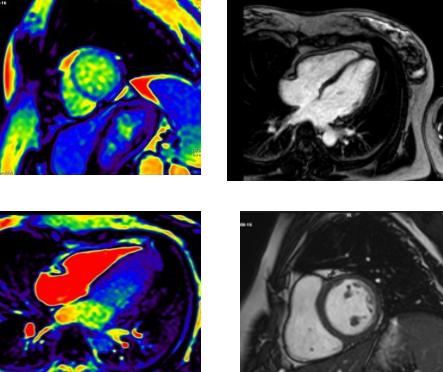

新年伊始,心五科接診了這樣一名年輕女性患者。患者受涼1周后出現心慌、氣短不適,既往無危險因素及心臟病史,入院后查動態心電圖提示:頻發性室性早搏伴頻發短陣室性心動過速,但患者心肌酶譜及心臟彩超均未經明顯異常。患者究竟是什么原因導致此類惡性心律失常呢?是冠心病?心肌病?心肌炎?還是遺傳性心臟病?在心五科主任李陽副教授、馮韓章責任總醫師及科室醫生的分析討論后,最終決定于2021年1月21日為患者進行心臟磁共振檢查。在醫學影像科張利安責任總醫師、蔡雷主治醫師認真讀片,院長助理兼醫學影像科主任劉連鋒教授最終確認后,考慮心肌致密化不全。可是心肌致密化不全又是什么樣的一種疾病呢?

心肌致密化不全(海綿心肌病)是一種罕見的特殊類型的心肌病,屬于先天性、遺傳性心肌病,它表現為以心室內異常粗大的肌小梁和交錯的深隱窩為特征的一種與基因相關的遺傳性心肌病。心臟是由非常密集的肌肉細胞組成的,如果胎兒或后天疾病導致心肌細胞空間增大,即心臟沒有致密的肌肉結構,導致心肌致密化不完全,收縮力下降,心功能或心率改變,部分患者后果嚴重。一般主要是累及心臟的左心室,臨床表現多樣,從無癥狀到進行性心功能惡化,充血性心力衰竭,心律失常,甚至猝死。

心肌致密化不全過去主要靠超聲心動圖診斷,但由于分辨率問題,部分患者敏感性較低,有時需要經食道UCG或心肌聲學造影,心臟MRI對NVM診斷敏感性可達86%,特異性達99%。經過明確診斷,可提高患者對疾病的重視,提高醫生對患者疾病的認識,為患者提供更優化的治療措施及預后判斷。